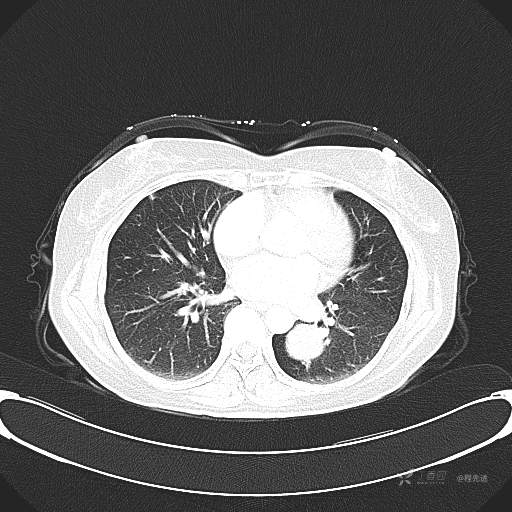

6月特别精彩病例|中老年女性,体检发现左肺下叶肿块,期待你的精彩演绎【病理公布】

患者性别:女

患者年龄:57岁

简要病史:体检发现

CT增强

平扫CT值约40HU(未上传图像),增强后动脉期CT值约70HU,静脉期CT值约97HU。

肺硬化性血管瘤 (20)